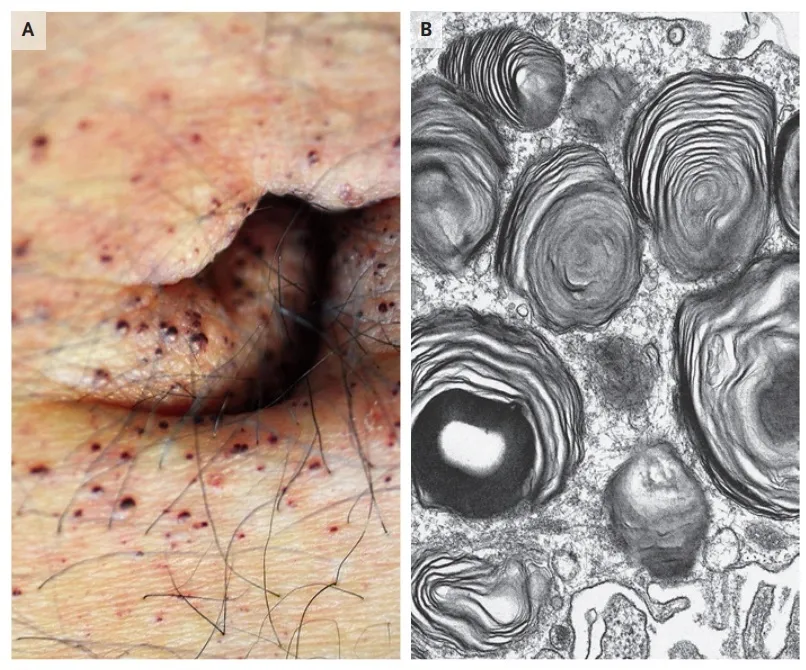

Proteinúria persistente, dor neuropática e lesões cutâneas podem parecer desconexas, mas, quando analisadas em conjunto, revelam a Doença de Fabry. Este caso ilustra como a integração entre clínica, biópsia renal, estudo enzimático e genética conduz a um diagnóstico preciso e a um manejo precoce, com impacto direto no prognóstico do paciente e de sua família.

Valkercyo Feitosa

11 meses atrás